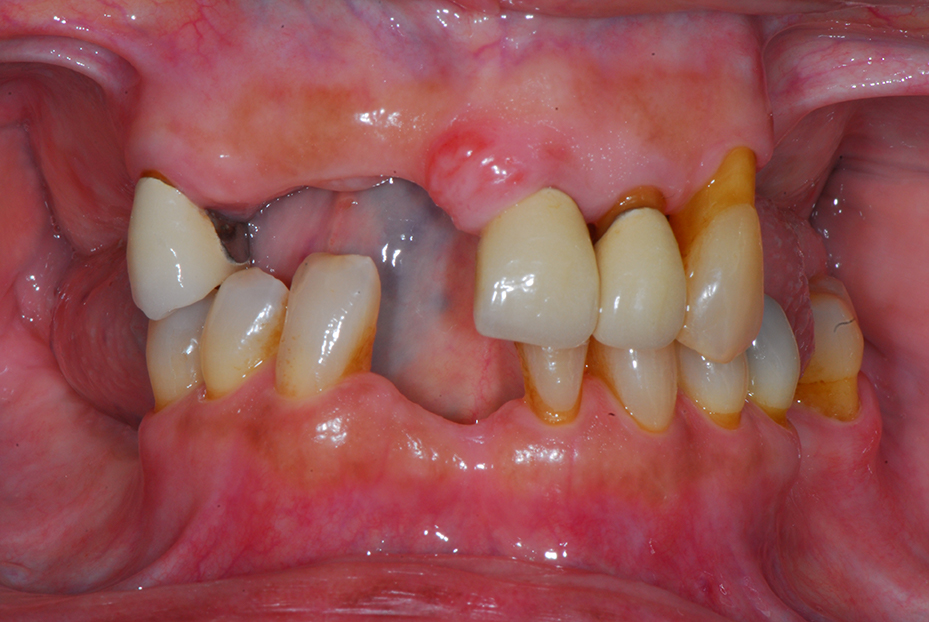

Replacement of all upper teeth with implant supported ceramic bridgework, and implant crowns to replace the missing lower teeth.

Before